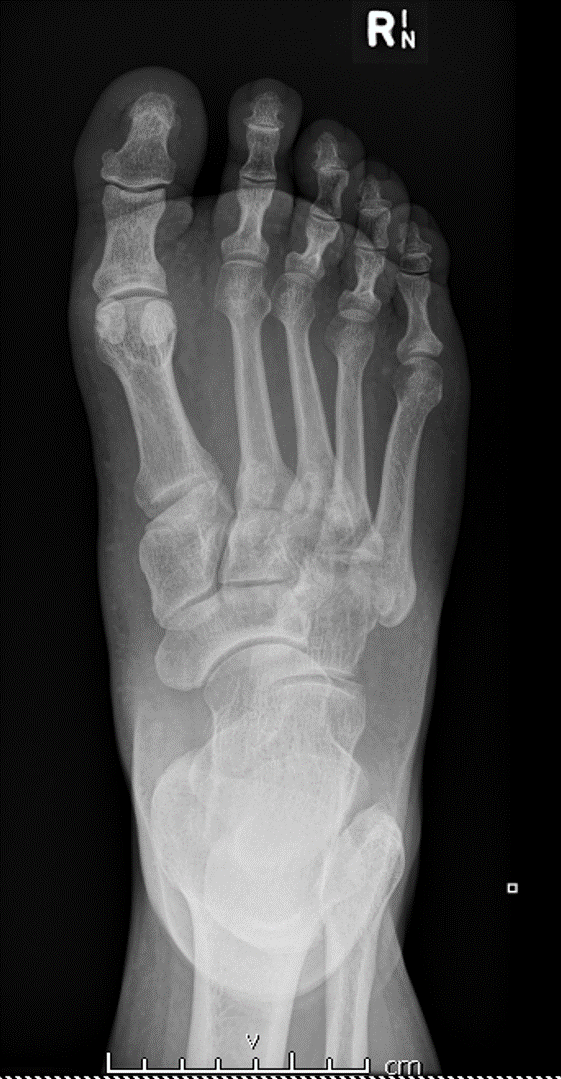

lisfranc损伤是常见的跗跖关节骨折和/脱位。

CASE 2 M40 足伤

初始X线片